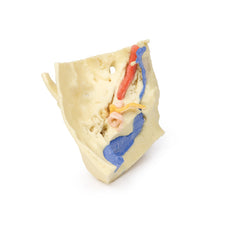

3D Printed Head and Visceral Column of the Neck

The face: On the right side of the head the parotid gland has been removed to reveal the facial nerve and all its branches (temporal, zygomatic, buccal, marginal mandibular and cervical) and demonstrate the spatial relations of structures embedded in the gland from superficial to deep (facial nerve, retromandibular vein, external carotid artery). In the surrounding region the temporalis, masseter and posterior belly of digastric are exposed, as are and the facial artery, transverse facial artery and superficial temporal artery. The facial vein and transverse facial vein are clearly visible uniting to form the common facial vein which is joined by the retromandibular vein to form the external jugular vein.

Viewed from the anterior aspect the face has been dissected to display some of the facial muscles around the mouth (buccinator [on the left], orbicularis oris and zygomaticus major). On the left side of the infratemporal fossa has been open to expose the medial and lateral pterygoids.

The lateral pterygoid is divided to show the mandibular division of the trigeminal nerve dividing into the lingual nerve and the inferior alveolar branch. Also on the left side the branches of the ophthalmic division of the trigeminal that supply the skin above the eyebrows and scalp (supraorbital [left only] and supratrochlear nerves [both sides]) are dissected. The submandibular gland is clearly visible below the mandible on both sides as are the facial arteries and veins as they course over the mandible.

The neck: The musculoskeletal portion of the neck have been removed to display the pharynx posteriorly, the larynx anteriorly, and the neurovascular bundles laterally. The suprahyoid and infrahyoid muscles can be seen on the neck, as well as the cricothyroid muscle.

When looking up the length of the trachea from below, the vocal folds are visible. The hypoglossal nerve can be seen winding around the lateral surface of the external carotid artery and the external branch of superior laryngeal nerve is seen descending in the neck. The internal jugular vein, the common carotid artery and its bifurcation into external and internal carotid arteries are clearly seen on both left and right. The vagus nerve in the carotid sheath is also visible. The ansa cervicalis is visible emerging below the digastric muscle and descending on the surface of the internal jugular vein. The internal branch of the superior laryngeal nerve can be seen below the superior thyroid artery on the left. The superior thyroid artery branching from the external carotid artery is seen descending in the anterior neck. The internal branch of the superior laryngeal artery is visible on the left piercing the thyrohyoid membrane above the inferior constrictor where this muscle is attached to the hyoid bone.

Posterior view of the pharynx: The superior, middle and inferior pharyngeal constrictors are indicated on the pharynx wall. The oesophagus can be identified emerging from the lower end of the pharynx. The posterior horn of the hyoid bone acts as a useful landmark. The carotid sheath seen from behind clearly shows the vagus nerve and its pharyngeal branches on the left. The recurrent laryngeal nerve is briefly visible on the left lying medial to the inferior thyroid artery. The occipital arteries are visible as they curve around the mastoid process. The vertebral arteries are seen either side of the brainstem as they enter the foramen magnum. The cerebellum has been removed to allow the fourth ventricle to be exposed. The cut surfaces of the cerebellar peduncles are clearly visible. A large portion of the posterior inferior cerebellar artery on the right is still visible as it winds around around the brainstem.

Cranial Cavity: The left and right orbits have been opened to reveal the orbital nerves and vessels along with the eyes and optic nerves. The optic chiasm, optic tracts and the lateral geniculate bodies are retained thus showing a large part of the visual pathways. The brainstem is cut at the level of the superior colliculi on the left and slightly lower on the right. The olfactory tracts and bulbs are also demonstrated. The origins of many of the cranial nerves from the brainstem are clearly visible.

3D Printed Head and Visceral Column of the Neck

This 3D print specimen preserves a series of features of the head and visceral column of the neck:The face: On the right side of the head the parotid gland has been removed to reveal the facial nerve and all its branches (temporal, zygomatic, buccal, marginal mandibular and cervical) and demonstrate the spatial relations of structures embedded in the gland from superficial to deep (facial nerve, retromandibular vein, external carotid artery). In the surrounding region the temporalis, masseter and posterior belly of digastric are exposed, as are and the facial artery, transverse facial artery and superficial temporal artery. The facial vein and transverse facial vein are clearly visible uniting to form the common facial vein which is joined by the retromandibular vein to form the external jugular vein.

Viewed from the anterior aspect the face has been dissected to display some of the facial muscles around the mouth (buccinator [on the left], orbicularis oris and zygomaticus major). On the left side of the infratemporal fossa has been open to expose the medial and lateral pterygoids.

The lateral pterygoid is divided to show the mandibular division of the trigeminal nerve dividing into the lingual nerve and the inferior alveolar branch. Also on the left side the branches of the ophthalmic division of the trigeminal that supply the skin above the eyebrows and scalp (supraorbital [left only] and supratrochlear nerves [both sides]) are dissected. The submandibular gland is clearly visible below the mandible on both sides as are the facial arteries and veins as they course over the mandible.

The neck: The musculoskeletal portion of the neck have been removed to display the pharynx posteriorly, the larynx anteriorly, and the neurovascular bundles laterally. The suprahyoid and infrahyoid muscles can be seen on the neck, as well as the cricothyroid muscle.

When looking up the length of the trachea from below, the vocal folds are visible. The hypoglossal nerve can be seen winding around the lateral surface of the external carotid artery and the external branch of superior laryngeal nerve is seen descending in the neck. The internal jugular vein, the common carotid artery and its bifurcation into external and internal carotid arteries are clearly seen on both left and right. The vagus nerve in the carotid sheath is also visible. The ansa cervicalis is visible emerging below the digastric muscle and descending on the surface of the internal jugular vein. The internal branch of the superior laryngeal nerve can be seen below the superior thyroid artery on the left. The superior thyroid artery branching from the external carotid artery is seen descending in the anterior neck. The internal branch of the superior laryngeal artery is visible on the left piercing the thyrohyoid membrane above the inferior constrictor where this muscle is attached to the hyoid bone.

Posterior view of the pharynx: The superior, middle and inferior pharyngeal constrictors are indicated on the pharynx wall. The oesophagus can be identified emerging from the lower end of the pharynx. The posterior horn of the hyoid bone acts as a useful landmark. The carotid sheath seen from behind clearly shows the vagus nerve and its pharyngeal branches on the left. The recurrent laryngeal nerve is briefly visible on the left lying medial to the inferior thyroid artery. The occipital arteries are visible as they curve around the mastoid process. The vertebral arteries are seen either side of the brainstem as they enter the foramen magnum. The cerebellum has been removed to allow the fourth ventricle to be exposed. The cut surfaces of the cerebellar peduncles are clearly visible. A large portion of the posterior inferior cerebellar artery on the right is still visible as it winds around around the brainstem.

Cranial Cavity: The left and right orbits have been opened to reveal the orbital nerves and vessels along with the eyes and optic nerves. The optic chiasm, optic tracts and the lateral geniculate bodies are retained thus showing a large part of the visual pathways. The brainstem is cut at the level of the superior colliculi on the left and slightly lower on the right. The olfactory tracts and bulbs are also demonstrated. The origins of many of the cranial nerves from the brainstem are clearly visible.